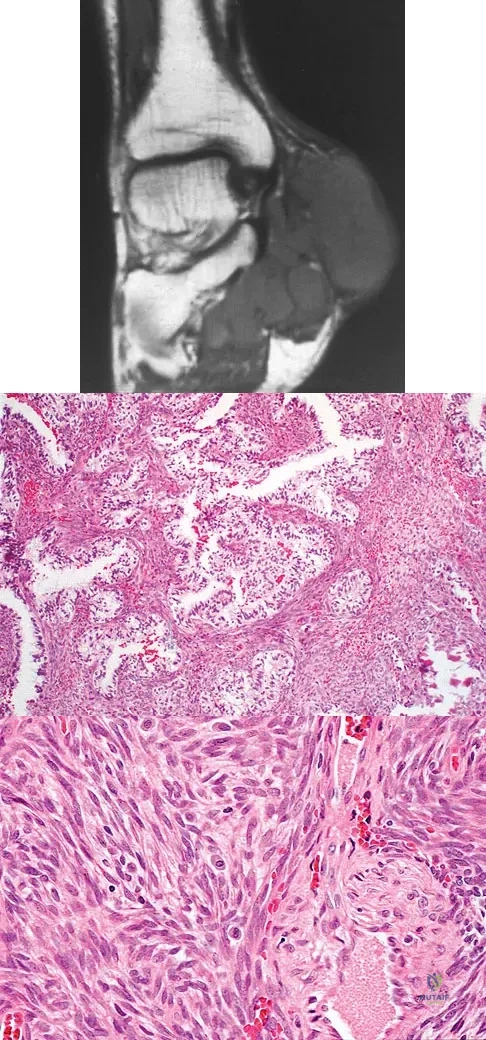

A 23-year-old man has had right posterolateral knee pain and occasional lateral calf dysesthesias for the past 8 months. A radiograph, CT scan, MRI scans, and a biopsy specimen are shown in Figures 62a through 62e. What is the most likely diagnosis?

A 40-year-old man has a painless mass around his left ankle. He notes minimal growth over the past year. An MRI scan is shown in Figure 73a, and biopsy specimens are shown in Figures 73b and 73c. What is the most likely diagnosis?